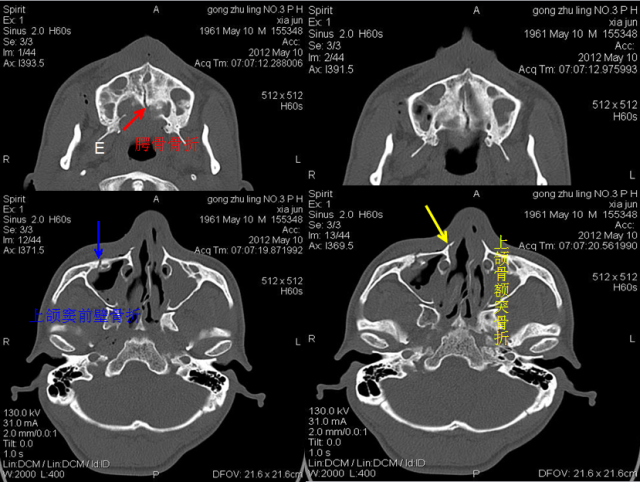

骨折篇

定义:骨折{Fracture}是指骨的完整性和连续性的折裂或粉碎。包括创伤性骨折、疲劳性骨折和病例理性骨折。 临床上以创伤性骨折*常见。